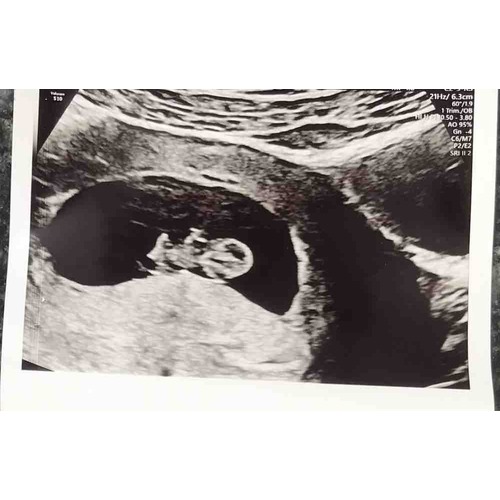

Lief dat je het vraagt! Het hartje klopt hartstikke mooi , steek in zij/rug ...

Wat fijn! Gefeliciteerd 馃コ